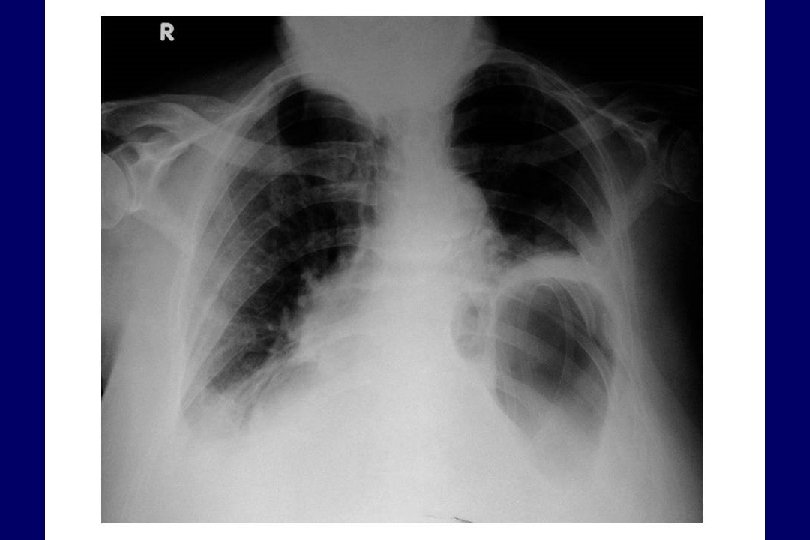

Basit Pnömotoraks Mediasten orta hatta Plevral sınır Eşit yükseklikte diafragmlar 1